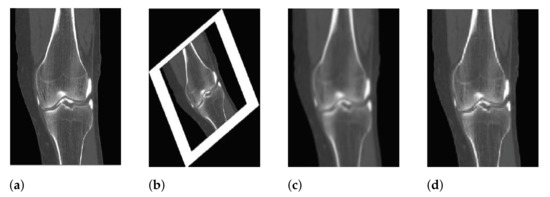

3.2. Feature Extraction

3.2.2. Key Points Orientation Assignment